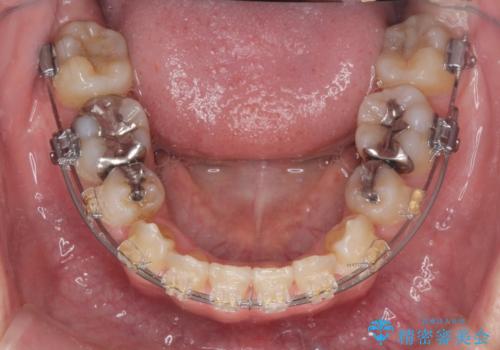

八重歯を矯正治療で治したい!

- 八重歯・がたつきのある歯並びの改善を求めて来院されました。

全部の歯が入り切るスペースがなかったため、小臼歯4本を抜去しワイヤーを用いたマルチブラケット矯正を選択しました。

歯並びの改善と共に、歯ブラシがしやすくなった!と喜んでいただくことができました。